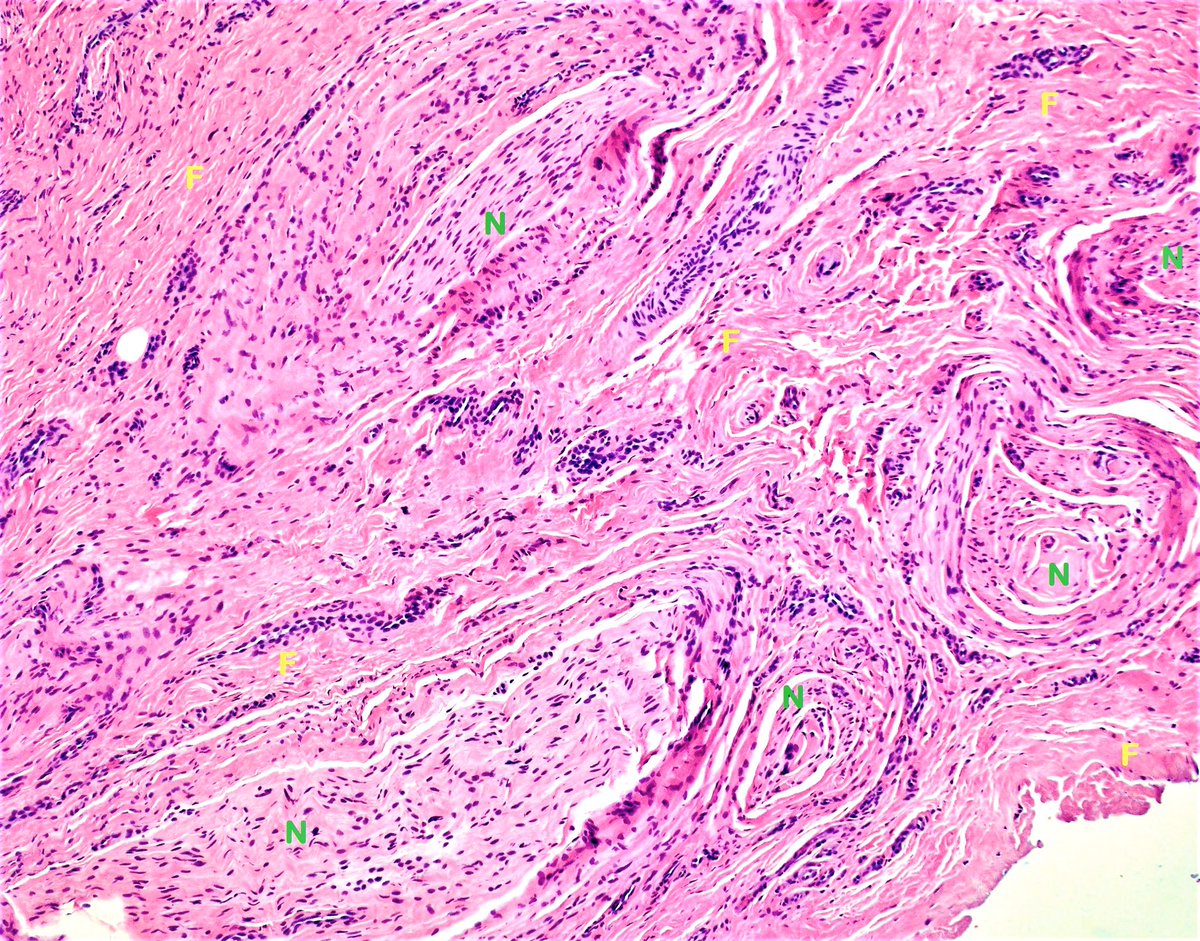

Morton Neuroma Pathology

Morton Neuroma Pathology / Troy watson, m.d., serving henderson nv, las vegas nv and the surrounding area.